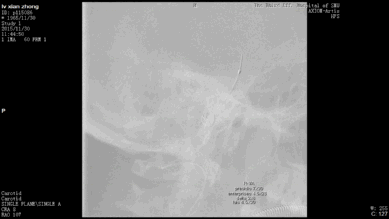

今天为大家分享的是“强生医疗CNV-神经介入专栏”第二十五期,由南方医科大学第三附属医院神经外科主任黄理金教授带来的“Enterprise支架辅助栓塞动脉瘤的优势”精彩讲课视频及PPT,欢迎观看。文章仅代表作者个人观点,如有不同见解,欢迎同道斧正!